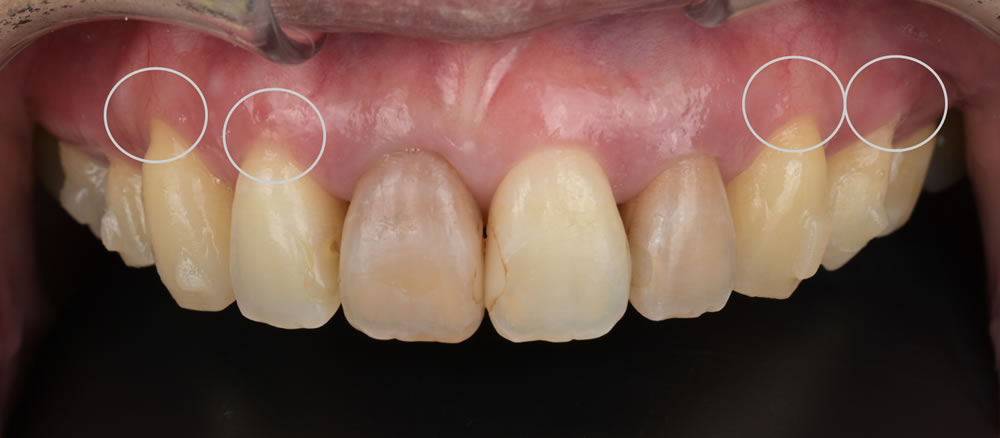

下がった歯肉を根面被覆術で改善した症例 こちらの患者さまは、下がった歯肉により歯がしみるとのことでしたので、再生療法の治癒待ちの9ヵ月の間に、上顎前歯のPhenotype Modification Therapy(フェノ […]